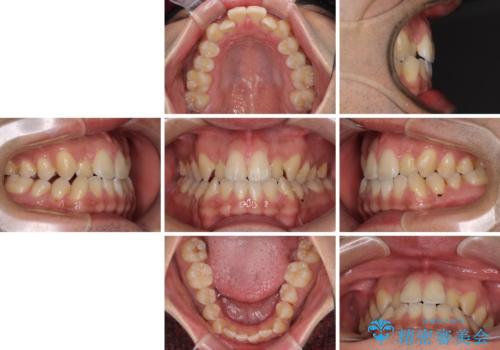

- 前歯のデコボコを気にして来院された患者様です。

歯列としてはワイヤー装置でもインビザラインでも対応可能でしたが、インビザラインが苦手とする上顎側切歯(真ん中から2番目の歯)の舌側転位が顕著でした。

治療の確実性を上げるために、インビザライン開始前に上顎のワイヤー装置にて舌側転位を解消し、その後インビザラインにて矯正治療を行うこととしました。

前歯のデコボコが早めに改善され、スムーズに治療を終えることができました。